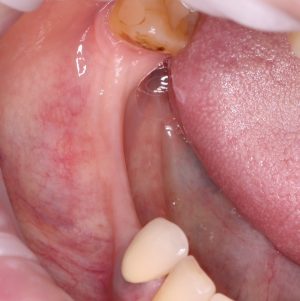

Я постараюсь показать вам, почему из этого:

получается это:

с минимальными затратами сил, нервов и денег. Этого не объяснить в рамках видеофильма или показа отдельного клинического случая. Это невозможно прочувствовать на челюсти барана или корке апельсина. В конце концов, если кто-то из докторов пожелает увидеть это «вживую», так сказать, с эффектом полного присутствия — очень скоро мы возобновим Индивидуальный Практический Курс и… добро пожаловать!